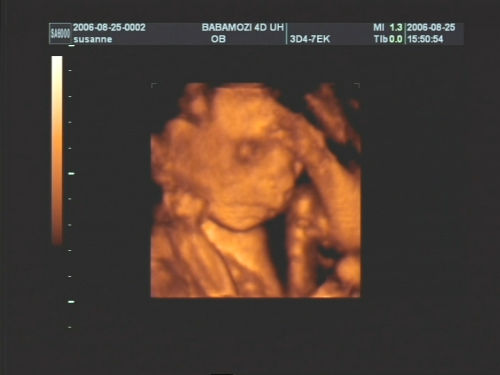

Pár kép:)

És akkor jöjjenek a képek:

Nem tudtam betelni velük,és nem tudtam választani közülük,azért van ilyen sok:

Kép Olyan kis szégyellős volt a drága,hogy állandóan takargatta a szemeit:Kép

És akkor az egyértelmű jelek:

Kép